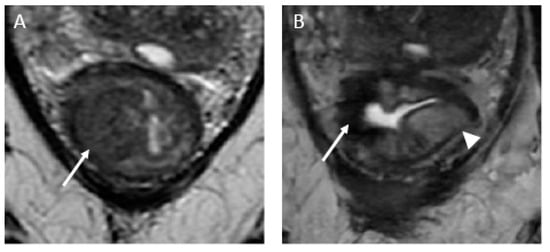

- iCR characterizes the scenario where tumor volume experiences a reduction, but discernible residual tumor persists. This response type manifests through persistent diffusion restriction and the persistence of T2 intermediate signal within the tumor bed (Figure 4).